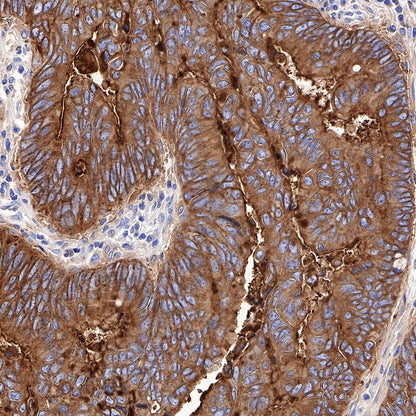

IHC shows positive staining in paraffin-embedded human colon. Anti-CEA(CD66e) antibody was used at 1/1000 dilution, followed by a Goat Anti-Rabbit IgG H&L (HRP) ready to use. Counterstained with hematoxylin. Heat mediated antigen retrieval with Tris/EDTA buffer pH9.0 was performed before commencing with IHC staining protocol.

IHC shows positive staining in paraffin-embedded human colon cancer. Anti-CEA(CD66e) antibody was used at 1/1000 dilution, followed by a Goat Anti-Rabbit IgG H&L (HRP) ready to use. Counterstained with hematoxylin. Heat mediated antigen retrieval with Tris/EDTA buffer pH9.0 was performed before commencing with IHC staining protocol.